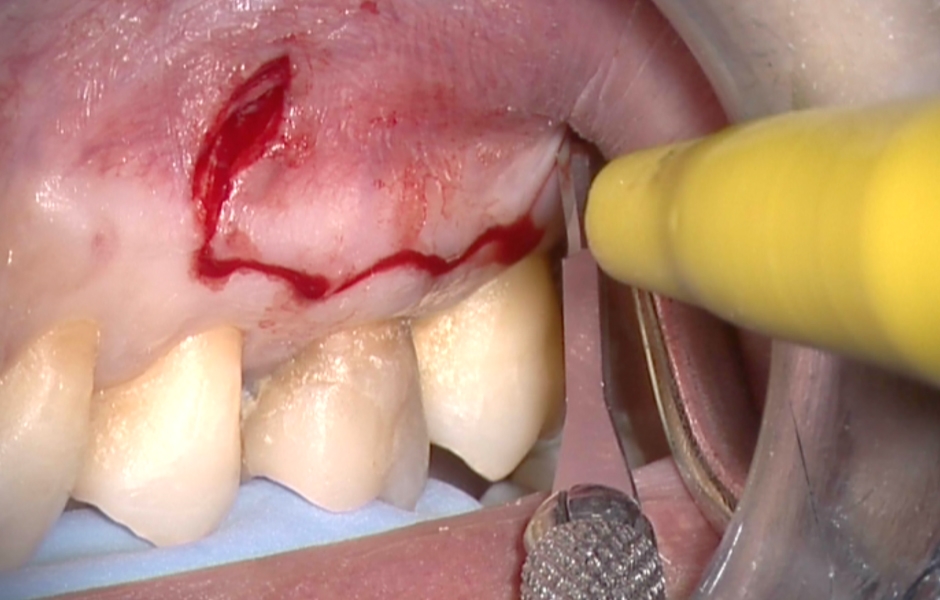

Obr. 1.2: Submarginální incize.

Obr. 4.2: Submarginální lalok.